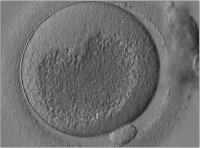

Die Bedeutung der Morphologie der Oozyte hinsichtlich ihres weiteren Entwicklungspotentials

Journal für Reproduktionsmedizin und Endokrinologie - Journal of Reproductive Medicine and Endocrinology 2006; 3 (1): 17-23 Volltext (PDF) Summary Abbildungen